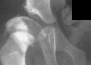

Physical exam showed the right hip to be dislocated. X-rays demonstrated

a dislocation of the right hip without the presence of an ossific nucleus

on the right side suggesting ischemic necrosis.

Following traction, open reduction was repeated, with satisfactory results;

however subsequent radiographs show an irregular pattern of growth with

a tendency for subluxation even though it was treated part time in an abduction

brace.